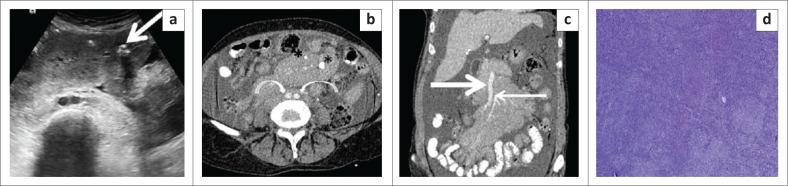

The mesentery is a broad fan-shaped fold of peritoneum that suspends the loops of small intestine from the posterior abdominal wall. Although primary neoplasms arising in the mesentery are rare, the mesentery is a major avenue for the dissemination of tumours, which can spread through hematogenous, lymphatic, direct or peritoneal seeding. Imaging helps in the diagnosis of these tumours and aids in directing appropriate treatment by assessing their size, extent and relationship with adjacent structures. The aim of this article is to describe the spectrum of imaging findings of the various mesenteric lesions using ultrasound and CT.

Evaluation of the mesentery is often neglected during routine ultrasound (US) because of inadequate training and unfamiliarity with the common US features encountered with mesenteric disease. CT plays an essential role in the diagnosis of mesenteric disease. Knowledge of imaging characteristics of various mesenteric lesions helps in timely diagnosis and management.

肠系膜是腹膜的一个宽阔扇形褶皱,将小肠袢从腹后壁悬吊起来。虽然起源于肠系膜的原发性肿瘤很少见,但肠系膜是肿瘤播散的主要途径,肿瘤可通过血行、淋巴、直接蔓延或腹膜种植扩散。影像学有助于这些肿瘤的诊断,并通过评估其大小、范围以及与相邻结构的关系来指导适当的治疗。本文旨在描述使用超声和CT对各种肠系膜病变的影像学表现范围。

由于培训不足以及对肠系膜疾病常见超声特征不熟悉,在常规超声(US)检查中对肠系膜的评估常常被忽视。CT在肠系膜疾病的诊断中起着至关重要的作用。了解各种肠系膜病变的影像学特征有助于及时诊断和处理。